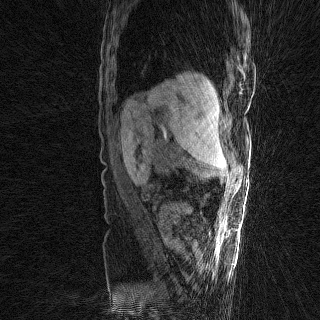

Deep neural networks for medical image reconstruction are traditionally trained using high-quality ground-truth images as training targets. Recent work onNoise2Noise (N2N) has shown the potential of using multiple noisy measurements of the same object as an alternative to having a ground truth. However, existing N2N-based methods cannot exploit information from various motion states, limiting their ability to learn on moving objects. This paper addresses this issue by proposing a novel motion-compensated deep image reconstruction (MoDIR) method that can use information from several unregistered and noisy measurements for training. MoDIR deals with object motion by including a deep registration module jointly trained with the deep reconstruction network without any ground-truth supervision. We validate MoDIR on both simulated and experimentally collected magnetic resonance imaging (MRI) data and show that it significantly improves imaging quality.

翻译:用于医学图像重建的深神经网络传统上是用高质量的地面真实图像作为培训目标来培训的。最近关于噪音2噪声(N2N)的工作表明,有可能使用同一物体的多重噪音测量来替代地面真相;然而,现有的N2N方法不能利用来自各种运动状态的信息,限制了它们了解移动物体的能力。本文件通过提出一个新的运动补偿深度图像重建(MoDIR)方法来解决这一问题,该方法可以使用来自若干未登记和吵闹的测量数据的信息进行培训。MDIR处理物体运动问题的方式是,在没有地面真相监督的情况下,与深层重建网络共同培训一个深层登记模块。我们在模拟和实验收集的磁共振成像(MRI)数据上验证了MDIR,并表明它大大提高了成像质量。